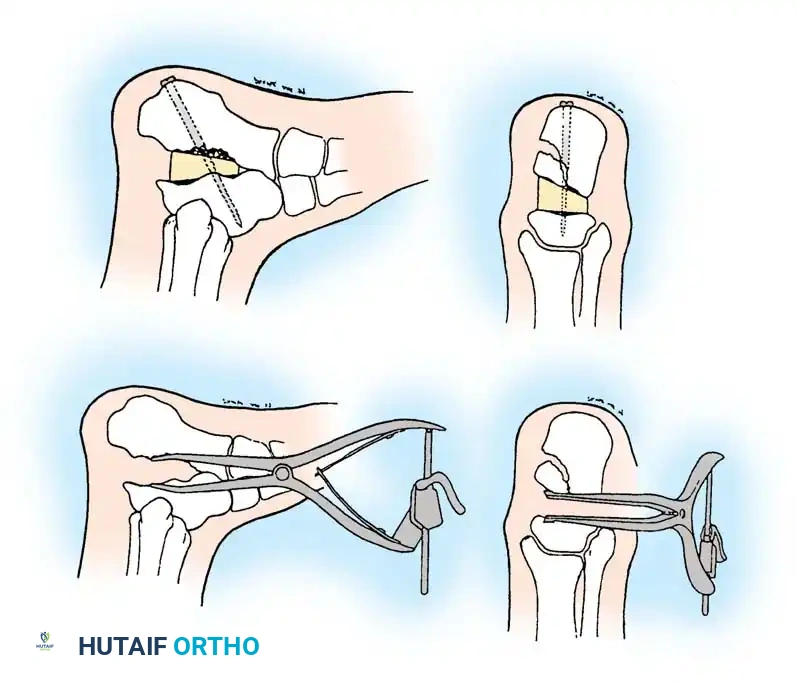

2. Calcaneal Osteotomy and Realignment Arthrodesis (Type II & III)

Intraoperative marking of the planned calcaneal osteotomy lines to correct varus/valgus malalignment.

Levering and distraction of the osteotomy site to restore calcaneal height and correct the talar declination angle.

The technique involves a lateral decompression, medial subtalar capsulotomy, and aggressive distraction of the subtalar joint. A lamina spreader is inserted to restore the talocalcaneal height.

Diagrammatic representation of subtalar distraction and realignment arthrodesis using a tapered wedge bone graft.

A tricortical iliac crest bone graft (or the resected lateral wall exostosis) is fashioned into a tapered wedge and impacted into the distracted subtalar joint. This bone block restores heel height, improves talar inclination, and corrects varus/valgus malalignment.